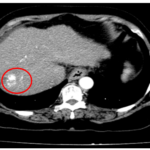

CASE LÂM SÀNG: CHẨN ĐOÁN BỆNH NHÂN MẮC HAI UNG THƯ: GIST RUỘT NON VÀ UNG THƯ TUYẾN GIÁP TẠI TRUNG TÂM Y HỌC HẠT NHÂN VÀ UNG BƯỚU, BỆNH VIỆN BẠCH MAI

Ca lâm sàng

GS.TS Mai Trọng Khoa; BSNT Hoàng Mạnh Đức, Ths Bùi Quang Lộc , PGS.TS Phạm Cẩm Phương, Bsck II Hoàng Anh, Trung tâm y học hạt nhân và...